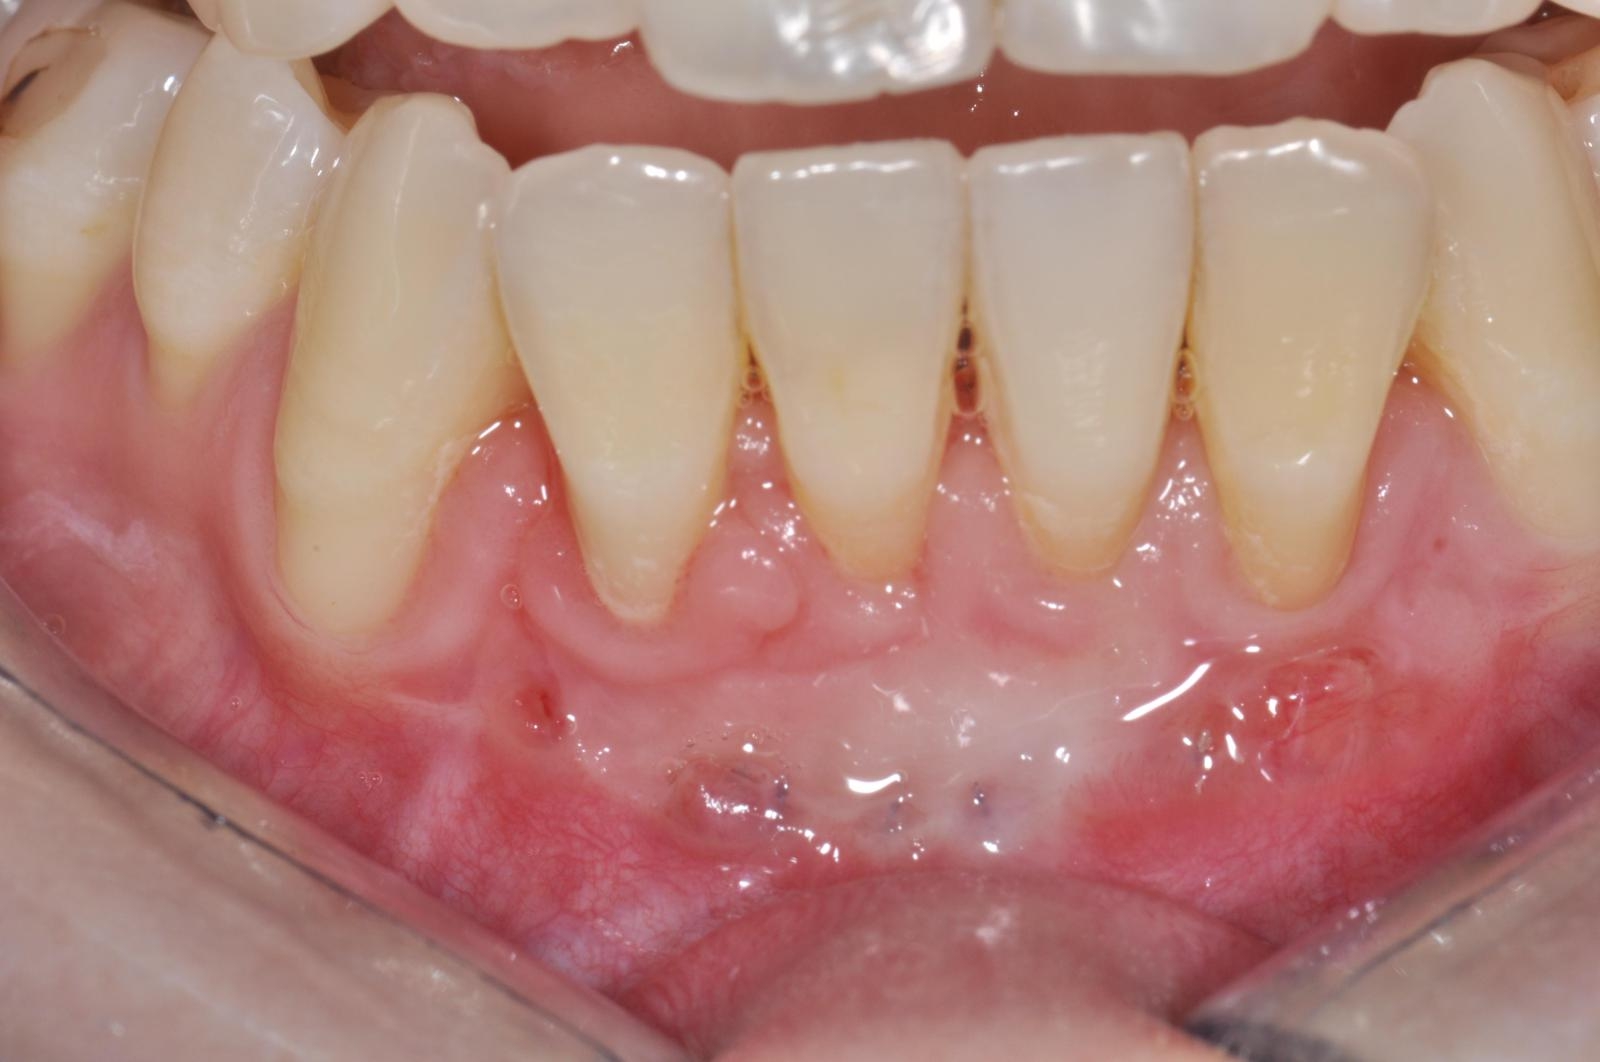

Celles-ci incluent la chirurgie à lambeaux pour un nettoyage en profondeur, la greffe gingivale ou conjonctive afin de renforcer les tissus, et la chirurgie du sourire gingival (ou "Gummy Smile") pour réharmoniser l’esthétique du sourire.

- Greffe Gingivales et conjonctives